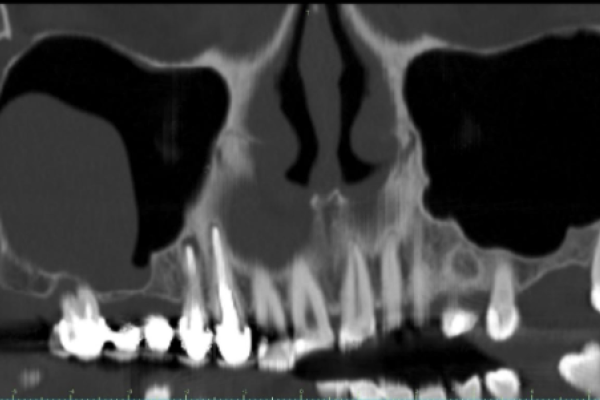

El equipo de Jiménez-Pascual y cols. a través de una actualizada revisión bibliográfica presenta los nuevos avances en la revitalización pulpar en dientes inmaduros. A continuación, se presentan dos casos clínicos. El primero de Beca y cols. analiza el comportamiento clínico, radiográfico e histomorfométrico del diente autólogo en la elevación de seno maxilar lateral de acceso lateral, acompañado de unas imágenes de la técnica y seguimiento de seis meses. Sánchez-Ruiz y cols. analizan el tratamiento quirúrgico de la patología pseudoquística sinusal a través de un caso clínico donde recogen las imágenes del diagnóstico, tratamiento y resolución a los seis meses.